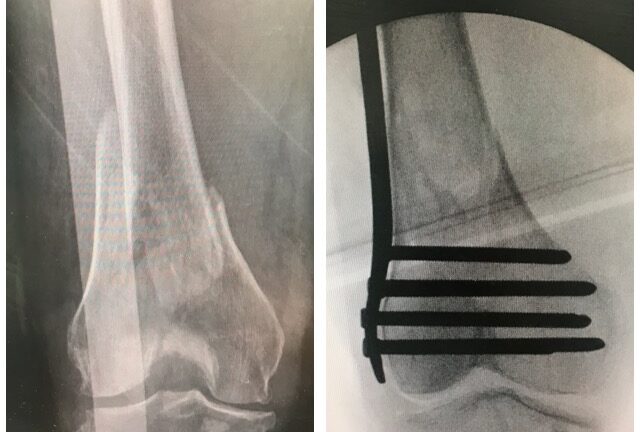

Säärimurtuma

Ennen – jälkeen